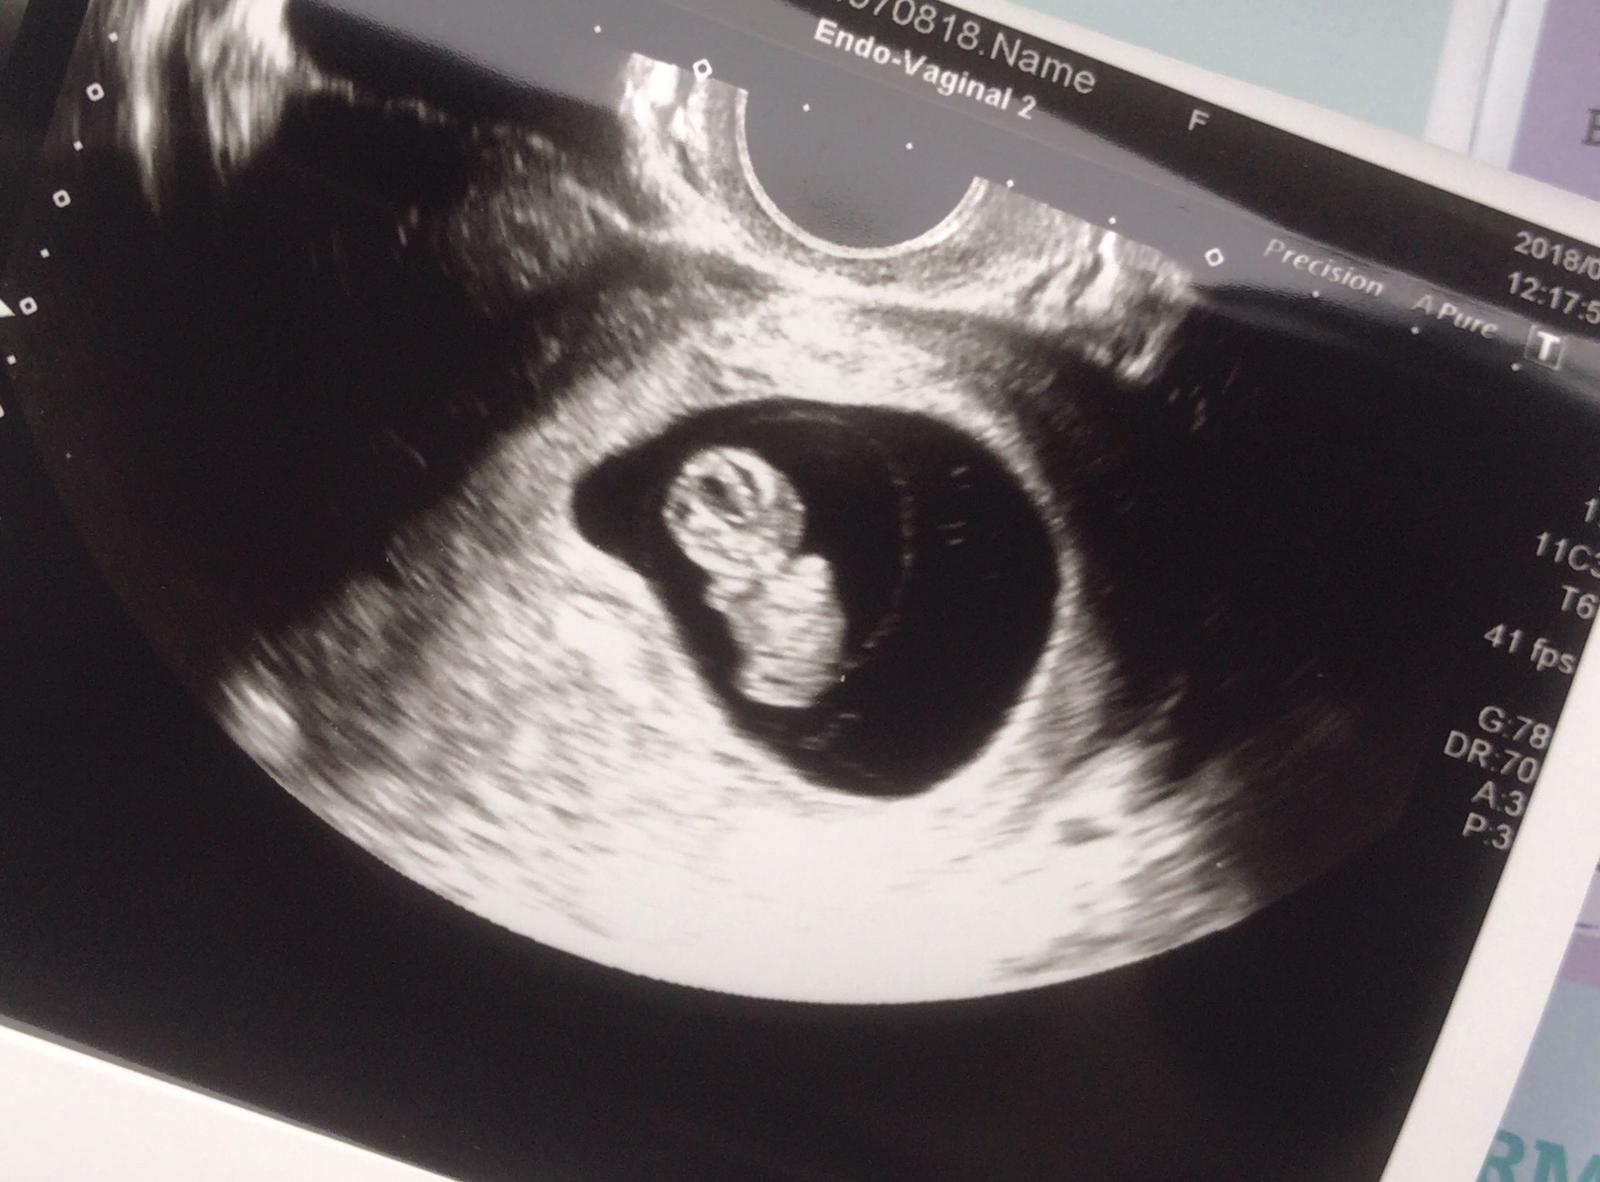

Ahoj holky ! Tak dnes po obědě nás čeká kontrolní ultrazvuk , naposledy jsme byli před 14 dni .. doufám , ze bude vše v pořádku , držte palce 😀

@veronika_2019 drzim palce, pak dej vedet, me to ceka ve ctvrtek 🙂

@jessulka to jsme na tom úplně stejně 😀 já jsem dnes také 9+3 tt , dnes mám kontrolní UTZ , protože můj doktor jede na dovolenou a chce mě ještě vidět , příští týden nás také čekají odběry a další UTZ na změření mimca, screening bude zřejmě 3.8 😀😀 já bych s sebou rada vzala přítele , tak uvidím co mi doktor řekne 🙂)